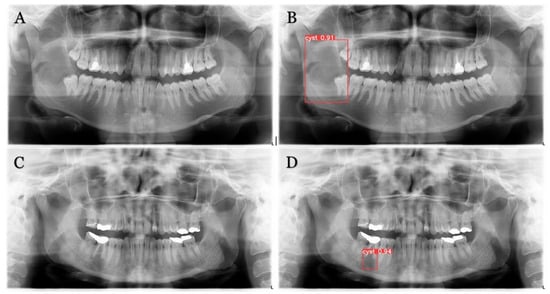

The trained model is capable of predicting bounding boxes, segmentation masks and probabilities, as shown in Figure 4 and Figure 5.

Figure 4. Model detection prediction of the radiolucent lesion in the lower jaw. (A), lesion in the ramus of the mandible (B), model successful detection of 91% (C), lesion in the corpus of the mandible (D), successful detection of 94%.